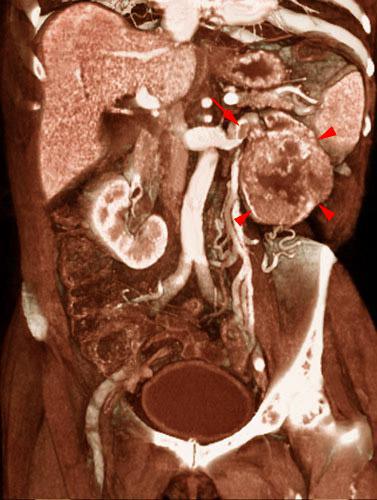

Tumor renal con trombosis venosa

VR seccional. Visión coronal anterior. AngioTC renal mostrando gran tumoración del polo renal inferior izquierdo (puntas de flecha). Se visualiza un trombo en la vena renal izquierda (flecha).